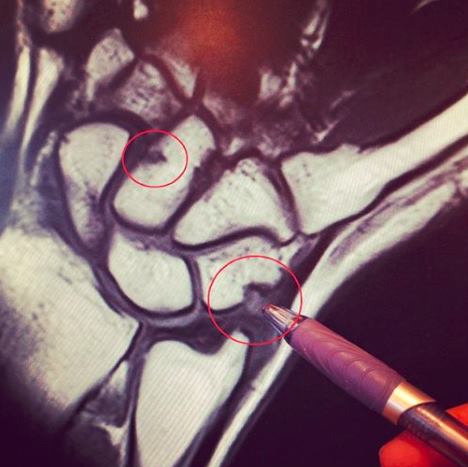

Marita Engzelius har nå fått undersøkt armen. Det viser seg at hun har hatt

skader i to av håndrotsbena i høyre hånd.

Marita

studerer MR-bildet av høyre hånd

Da jeg kom hjem til Norge, fikk jeg tatt MR. Jeg gjorde dette for å forsikre meg

om at jeg kun hadde en vanlig betennelse og ikke noe annet. Dessverre var ikke

dette tilfellet… Væskeansamling og hevelser inne i to av håndrotsbena i

håndleddet og i tillegg en kraftig senebetennelse. Jeg har blitt fortalt at

hadde jeg fortsatt å trene nå, hadde jeg dratt på meg et tretthetsbrudd.

Konklusjonen var at for å få de skadene jeg nå har pådratt meg, må jeg ha utsatt

håndleddet for en god del juling.

For the past seven weeks, I have been struggling with pain in my right wrist and

forearm. Last Tuesday, I had an MRI taken and now I have received the results…

It turns out I have bone-bruising in two of the bones in my right wrist; this is

the beginning of a potential stress fracture. Furthermore, the doctors also

confirmed tendonitis in my right arm.